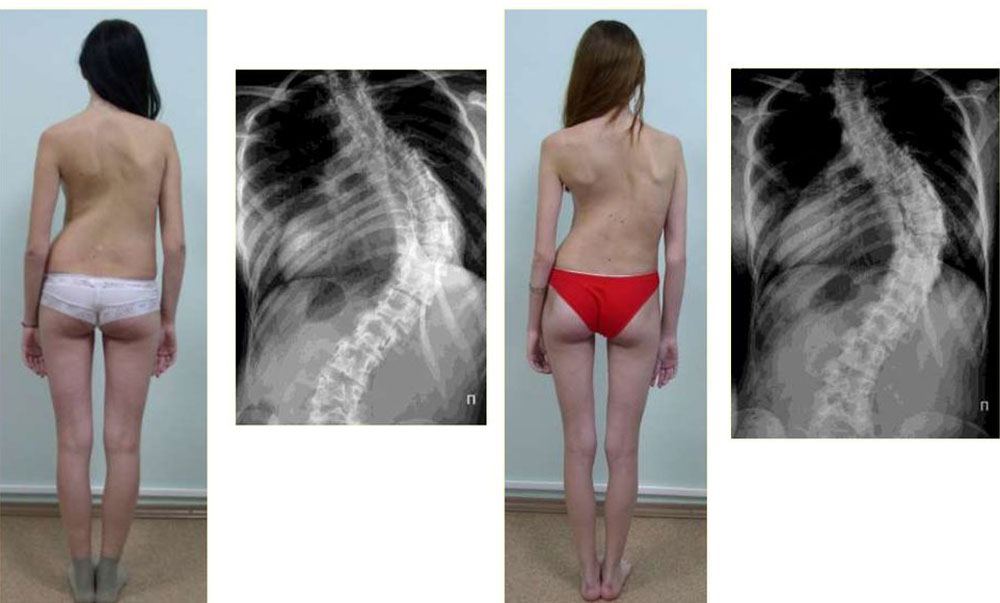

Mein Mitgefühl allen mit solchen Problemen. Ich habe vor einem halben Jahr von Veluflex erfahren. Den Rücken habe ich in 2 Monaten vollständig in den Griff bekommen. Hier meine Fotos:

Wir haben Veluflex für unsere Tochter bestellt. Sie hatte eine Wirbelsäulendeformation mit Verschiebung 3. Grades – Operation wurde vorgeschlagen, wir haben abgelehnt. Wir sind mit ihr zu den besten Ärzten in Deutschland, beste Tabletten – nichts hat so gewirkt wie Veluflex! Es hat sie in 2,5 Monaten geheilt. Unglaublich!